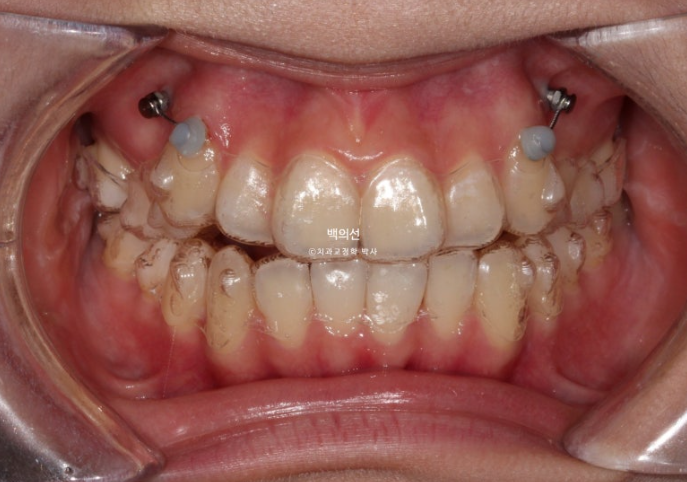

25.01

위에는 교정용 나사를 두 개 심어 송곳니 덧니를 가지런히 할 공간을 어금니 후방이동으로 얻기로 합니다.

클리피씨 장치를 붙인 사진이 없어 엑스레이로 대체합니다.

그렇게 클리피씨 장치를 붙인지 11개월째, 치료를 마무리 하였습니다.

25.07

교합은 좌우 정 1급을 달성했으며 좋습니다.